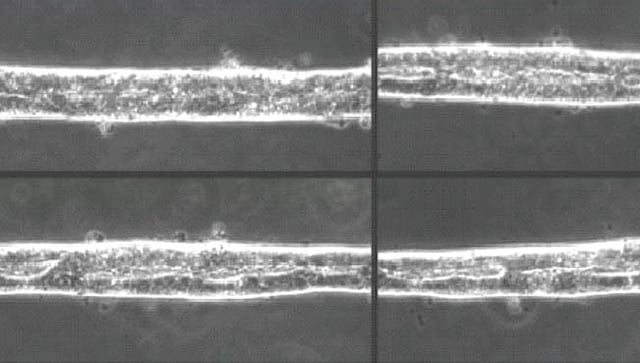

तेल अवीव : संशोधकांनी अनेक मानवी अवयवांसारखे कृत्रिम अवयवही प्रयोगशाळेत विकसित करण्यात यश मिळवलेले आहे. आता प्रथमच मानवी मध्यवर्ती चेतासंस्थेच्या सुरुवातीच्या टप्प्यांचे सूक्ष्म, थ्रीडी मॉडेलही बनवण्यात आले आहे. हे नवे मॉडेल म्हणजे 'ऑर्गनॉईड'चाच एक प्रकार आहे. जिवंत ऊतींचा वापर करून हे सूक्ष्म, थ्रीडी मॉडेल बनवले आहे. ते अकरा आठवड्यांच्या एखाद्या भ्रुणाच्या मेंदूची नक्कल करणारे आहे. चाळीस दिवसांच्या काळात हा कृत्रिम मेंदू प्रयोगशाळेत विकसित करण्यात आला.

त्यामध्ये सूक्ष्म अशा धडकणार्‍या हृदयापासून ते सूक्ष्म वृषणापर्यंतच्या अनेक अवयवांचा समावेश आहे. यापूर्वीही ब्रेन ऑर्गनॉईड्स बनवण्यात आलेले आहेत. मात्र, यावेळी प्रथमच भ्रुणीय मेंदूच्या सर्व तीन भागांची तसेच मणक्याची नक्कल प्रयोगशाळेत करण्यात आली. याबाबतच्या संशोधनाची माहिती 'नेचर' या नियतकालिकात देण्यात आली आहे. इस्रायलमधील विझमन इन्स्टिट्यूट ऑफ सायन्समधील न्युरोकेमिस्ट्रीचे प्राध्यापक आणि या संशोधनाचे प्रमुख ओर्ली रेनर यांनी याबाबतची माहिती दिली.

हे मेंदूचे मॉडेल अगदी खर्‍या मेंदूप्रमाणेच कार्य करते, असे त्यांनी सांगितले. त्याचा विकास मानवातील प्लुरीपोटेंट स्टेम सेल्स म्हणजेच मूळपेशींचा वापर करून करण्यात आला. मूळपेशी या शरीरातील अशा पेशी असतात ज्यांचे रूपांतर शरीरातील कोणत्याही अवयवांच्या पेशींमध्ये करता येते.